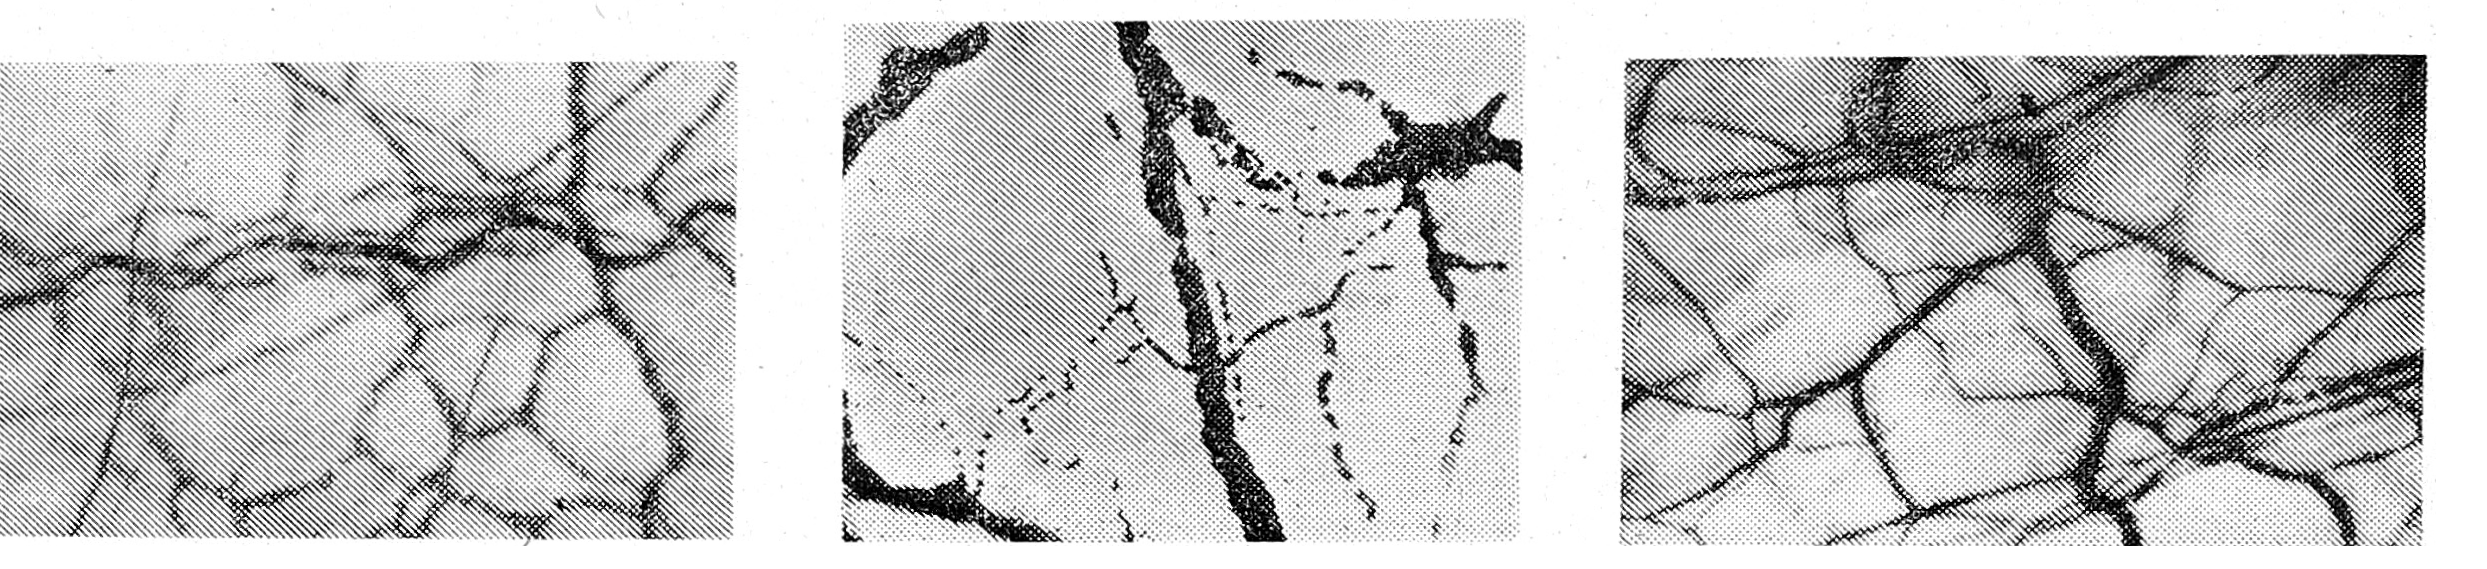

) Гипотонии микрососудов сопутствовали симптомы депонирования крови. В отдельных расширенных капиллярах скапливалось большое количество форменных элементов. При этом тонус посткапиллярных сфинктеров нередко был повышенным и форменные элементы выключались из циркуляции. Резко сокращалось число функционирующих капилляров, и движение форменных элементов осуществлялось в основном через артериовенозные шунты (рис. 1); Кровоток был резко замедленным, а в отдельных капиллярах наблюдалось его стазирование. Медленное движение форменных элементов способствовало слипанию эритроцитов и появлению агрегации форменных элементов (сладж-феномена). Закупорка агрегатами отдельных микрососудов и неадекватная капиллярная перфузия тканей приводили к недостаточному снабжению тканей кислородом. Напряжение кислорода в капиллярной крови равнялось 9,7±0,5 кПа (норма— 11,7 ± 0,6 кПа; Р<0,01).

Рис. 1, 2, 3. Микроциркуляторное русло бульбарной конъюнктивы при пищевой токсикоинфекции, осложненной гиповолемическим шоком II (рис. 1), III степени (рис. 2) и сразу после проведенной регидратационной терапии (рис. 3). Объектив Х 8, окуляр Х 7.

У 12 больных с декомпенсированным шоком (III степени) дефицит массы тела составлял 9% и более; АД и пульс не определялись; наблюдались анурия, гипотермия и другие признаки обезвоживания Ill—IV степени. В исследованных участках микроциркуляториого русла у всех больных были констатированы гипотония микрососудов, уменьшение числа функционирующих капилляров, закупорка их агрегатами (рис. 2). В большинстве капилляров кровоток отсутствовал и сохранялся только через артериовенозные шунты. В микрососудах у всех больных этой группы преобладала фильтрация и отмечался дополнительный выход жидкой части крови за пределы капиллярной стенки. Метаболический ацидоз был резко выраженным, pH у отдельных больных достигал 7,10—7,15.

На втором этапе лечения регидратацию производили по потерям и обычно осуществляли через рот растворами «Квартасоль» и «Трисоль», и только у Уз больных потребовалось повторное внутривенное введение препаратов. Другие медикаментозные средства (гормоны, вазопрессоры, сердечные) в лечении не использовались. Инфузия кристаллоидных растворов сопровождалась быстрым улучшением самочувствия. В первые полчаса исчезали судороги, прекращалась рвота, восстанавливались пульс и АД. К концу вливания купировался цианоз и восстанавливалось мочеотделение. При этом в микроциркуляторном русле вначале происходило восстановление тонуса артериол, скорости кровотока и числа функционирующих капилляров (рис. 3).